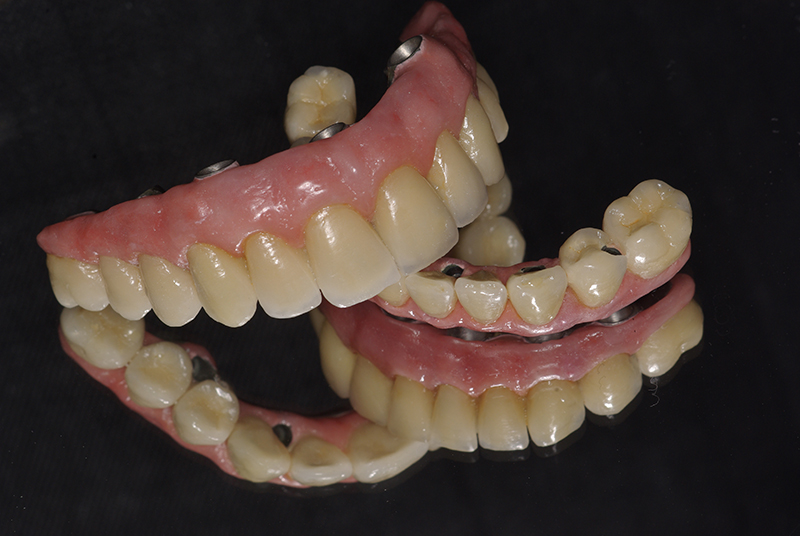

Utilizamos a tecnologia CAD CAM, um sistema avançado que possibilita a confecção precisa das próteses dentárias diretamente sobre os implantes. Esse método inovador garante um ajuste perfeito, um resultado estético superior e proporciona muito mais conforto e durabilidade. Com o CAD CAM, nossos pacientes contam com um processo mais rápido e previsível para alcançar o sorriso desejado.